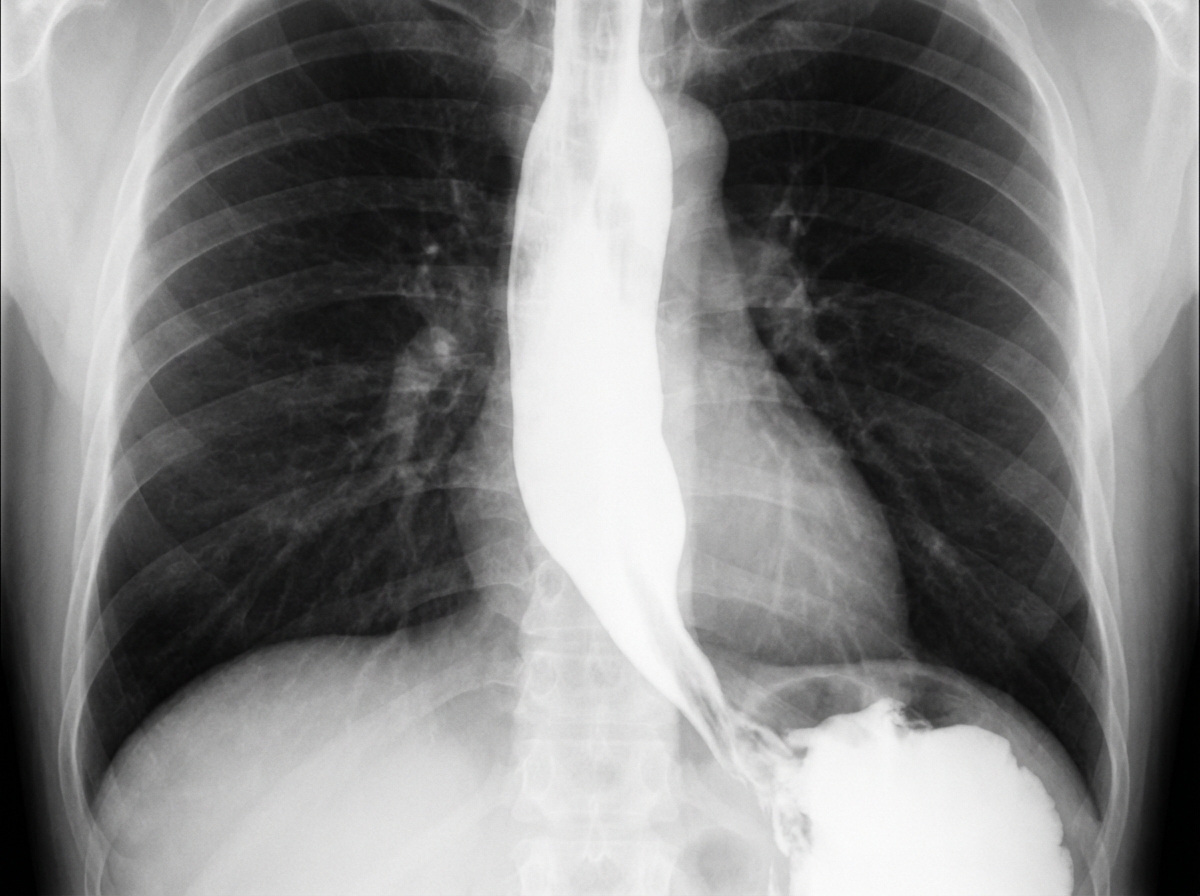

A 62-year-old man is referred to a gastroenterologist because of difficulty swallowing for the past 5 months. He has difficulty swallowing both solid and liquid foods, but there is no associated pain. He denies any shortness of breath or swelling in his legs. He immigrated from South America 10 years ago. He is a non-smoker and does not drink alcohol. His physical examination is unremarkable. A barium swallow study was ordered and the result is given below. Esophageal manometry confirms the diagnosis. What is the most likely underlying cause of this patient’s condition?

A 48-year-old man from Argentina presents to your office complaining of difficulty swallowing for the past few months. He is accompanied by his wife who adds that his breath has started to smell horrible. The patient says that he feels uncomfortable no matter what he eats or drinks. He also has lost 5 kg (11 lb) in the last 2 months. The patient is afebrile, and his vital signs are within normal limits. Physical exam is unremarkable. A barium swallow study along with esophageal manometry is performed and the results are shown in the image below. Manometry shows very high pressure at the lower esophageal sphincter. Which of the following is the most likely etiology of this patient’s symptoms?

Explanation: ***Chagas disease*** - The patient's history of living in **South America** and presenting with **dysphagia for both solids and liquids** (suggesting a motility disorder), along with the **barium swallow image showing esophageal dilation and a 'bird's beak' appearance** at the gastroesophageal junction, are highly characteristic of achalasia caused by Chagas disease. - Chagas disease, caused by *Trypanosoma cruzi*, leads to the destruction of **myenteric plexus neurons** in the esophagus, resulting in achalasia (failure of the lower esophageal sphincter to relax) and megaesophagus. *Pharyngoesophageal diverticulum* - This typically presents as **Zenker's diverticulum**, causing **difficulty initiating a swallow**, regurgitation of undigested food, and sometimes halitosis, which is different from the described dysphagia for both solids and liquids. - A Zenker's diverticulum would appear as a **pouch-like protrusion** in the posterior pharynx, not the diffuse esophageal dilation seen in the image. *Esophageal rupture* - Esophageal rupture (Boerhaave syndrome) is an acute, life-threatening condition associated with **severe chest pain, vomiting, and crepitus**, not a chronic, progressive dysphagia without pain. - Imaging would reveal **extravasation of contrast** into the mediastinum or pleural space, not the smooth dilation and distal narrowing observed. *Gastroesophageal reflux disease* - While chronic GERD can lead to **strictures** and dysphagia, it typically causes **heartburn**, regurgitation, and sometimes odynophagia, and the dysphagia is usually progressive for solids first. - The barium swallow would show reflux or a stricture, not the **classic achalasia findings** of a dilated esophagus tapering to a narrow distal segment. *Squamous cell carcinoma of the esophagus* - Squamous cell carcinoma usually presents with **progressive dysphagia, initially for solids**, and is often associated with weight loss, smoking, and alcohol use, none of which are present in this patient. - A tumor would typically appear as an **irregular, focal narrowing or mass** on barium swallow, not the smooth, diffuse dilation seen in this image.

Explanation: ***Trypanosoma cruzi infection*** - The patient's origin from **Argentina** (an endemic area for **Chagas disease**), coupled with symptoms of **dysphagia**, **weight loss**, and **halitosis**, strongly suggests **achalasia** secondary to *Trypanosoma cruzi* infection. - **Esophageal manometry** showing **very high pressure at the lower esophageal sphincter** and **absent or diminished peristalsis** is characteristic of achalasia, which in this context points to **Chagasic achalasia**. *Food allergy* - **Food allergies** typically present with acute symptoms such as **hives, angioedema, gastrointestinal upset**, or **anaphylaxis**, rather than chronic dysphagia and weight loss. - While eosinophilic esophagitis (a type of food allergy) can cause dysphagia, it usually presents with **esophageal strictures** or **rings** and is not associated with the distinct manometric findings of achalasia. *Outpouching of the mucosa and submucosa* - An **outpouching of the mucosa and submucosa** refers to a **Zenker's diverticulum**, which can cause dysphagia, halitosis, and regurgitation. - However, Zenker's diverticulum is typically located in the **upper esophagus** and would not cause increased lower esophageal sphincter pressure on manometry. *Malignant proliferation of squamous cells* - A **malignant proliferation of squamous cells** refers to **esophageal squamous cell carcinoma**, which can cause progressive dysphagia and weight loss. - While possible in an older patient, the characteristic manometric findings (high LES pressure) are more indicative of achalasia rather than a primary obstructive tumor. *Pyloric stenosis* - **Pyloric stenosis** is an obstruction at the gastric outlet, causing **projectile vomiting** and **weight loss**, primarily seen in infants. - In adults, it is usually due to peptic ulcer disease or malignancy and would not cause esophageal symptoms or increased lower esophageal sphincter pressure.